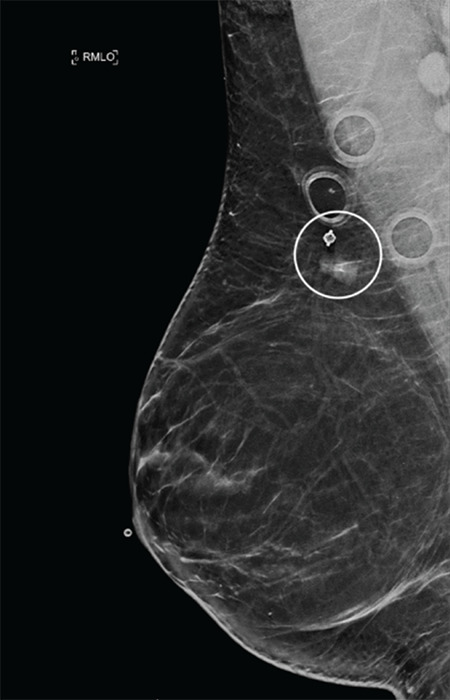

We present the case of a forty-year-old asymptomatic female with no personal or family history of breast cancer, who underwent a core needle biopsy (CNB) following the identification of a focal asymmetry in the right breast on screening mammography. Eight months later, a prominent adjacent vascular structure with a round outpouching was detected on breast ultrasound, confirmed as a post-biopsy pseudoaneurysm. Breast pseudoaneurysms, although exceedingly rare, result from inadvertent vessel puncture during core needle biopsies, particularly when larger gauge needles are used. They present as palpable, throbbing lumps in the breast and are well-defined heterogeneous structures that exhibit turbulent flow with a feeding artery on color Doppler imaging. This swirling sign showing a to-and-fro waveform is also known as the "yin-yang" sign on Doppler ultrasound. Post-CNB pseudoaneurysms in the breast, while rare, should be considered as potential complications following core need biopsy. Understanding their characteristic imaging features, risk factors, and available management options is essential for early diagnosis and appropriate treatment. This case underscores the importance of vigilance in biopsy procedures and the need for prompt recognition and intervention in case of such complications.

本病例是一名四十岁的无症状女性,无个人或家族乳腺癌病史,在乳房 X 光筛查中发现右侧乳房有局灶性不对称,随后接受了核心针活检(CNB)。八个月后,她在乳腺超声波检查中发现了一个突出的邻近血管结构,并伴有圆形外囊,证实为活检后假性动脉瘤。乳腺假性动脉瘤虽然极为罕见,但却是在核心针活检过程中不慎刺穿血管造成的,尤其是在使用较大规格的针头时。乳房假性动脉瘤表现为乳房内可触及的搏动性肿块,是界限清晰的异质结构,在彩色多普勒成像中表现为进血动脉的湍流。在多普勒超声检查中,这种显示往返波形的漩涡征也被称为 "阴阳 "征。乳腺核芯穿刺活检后假性动脉瘤虽然罕见,但应被视为核芯穿刺活检后的潜在并发症。了解假性动脉瘤的影像学特征、风险因素和可用的治疗方案对于早期诊断和适当治疗至关重要。本病例强调了在活检过程中保持警惕的重要性,以及在出现此类并发症时及时识别和干预的必要性。